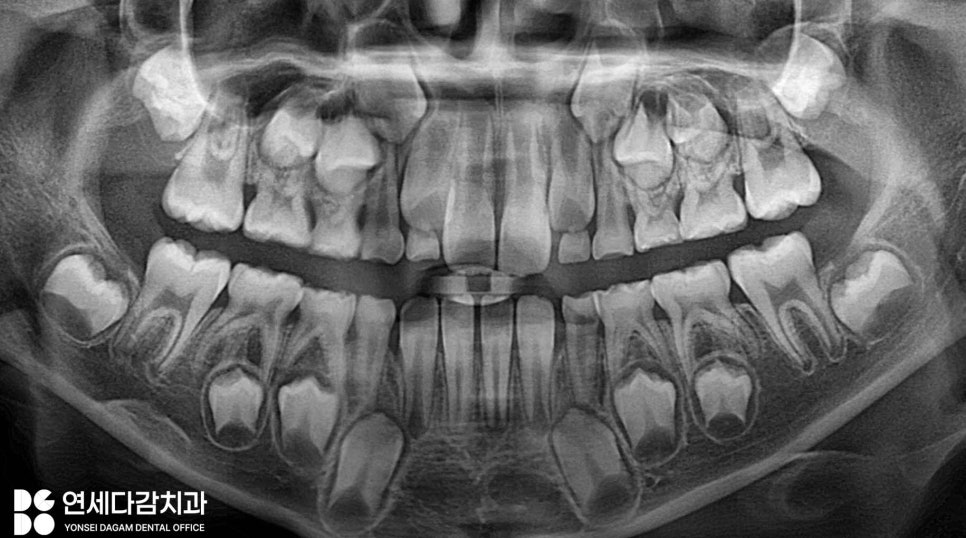

오금동 치과 에서는 엑스레이 사진과

구강 검진을 통해 정확히 진단하는

과정으로 진행합니다.